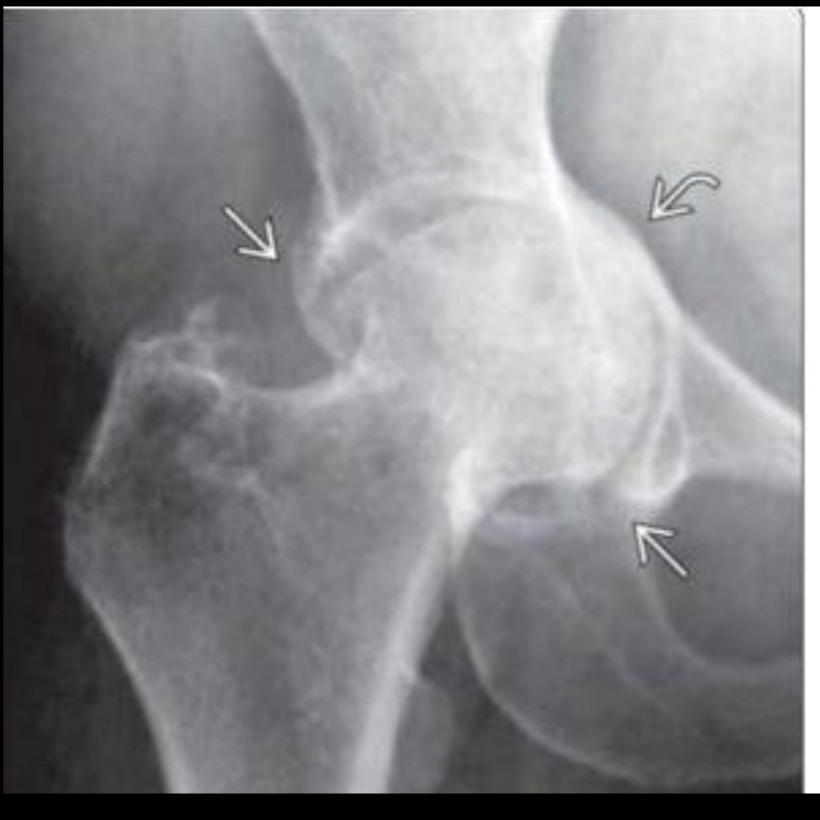

Datos de coxartrosis Rx

A

Disminución del espacio articular

Osteofitos

Esclerosis subcondral

Quistes subcontrates (geodas)

Deformidad

Coxartrosis